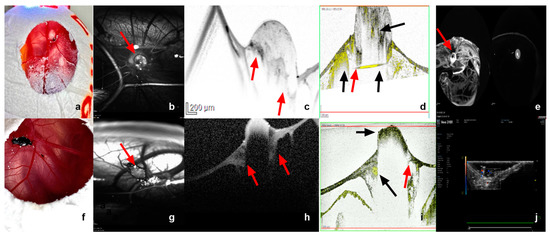

3.2.2. Infrared Imaging, Optical Coherence Tomography and Angiography, and Fluorescein Angiography

2.4.2. Optical Coherence Tomography and Infrared Imaging

2.4.3. Optical Coherence Tomography Angiography

2.4.4. Fundus Fluorescein Angiography

3.2.3. Image Analysis Using Image J